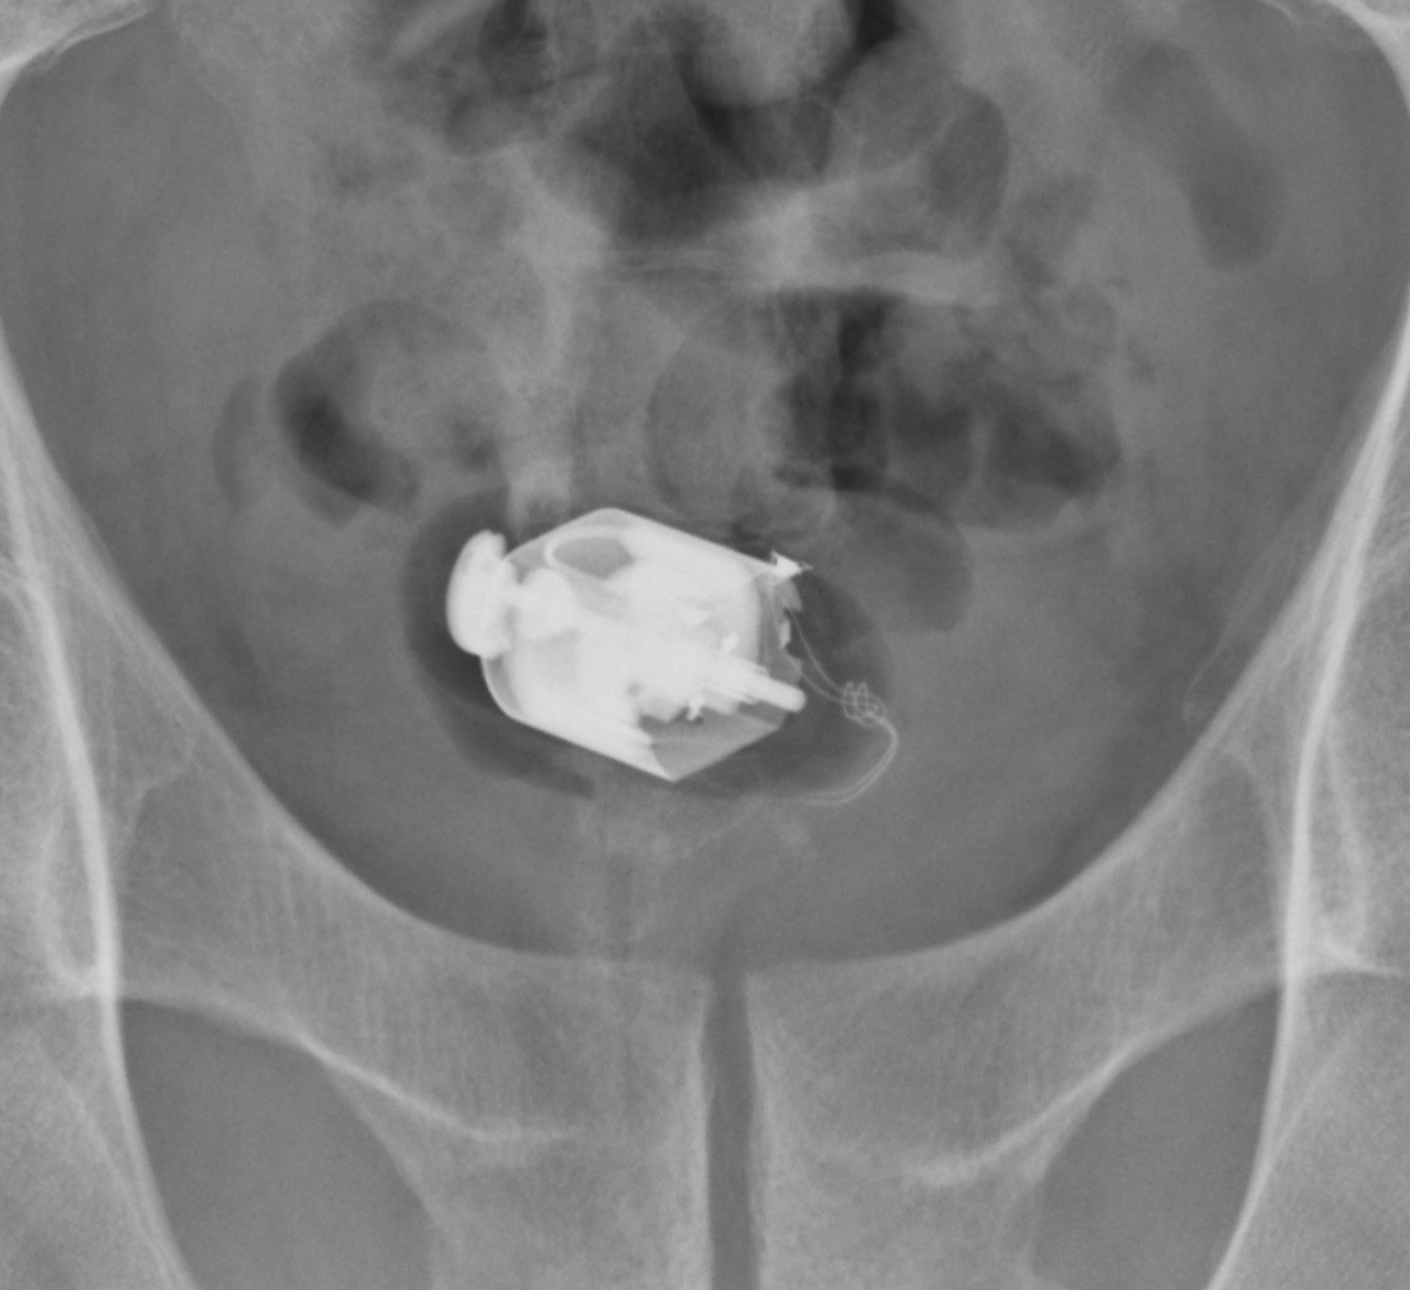

肛門異物